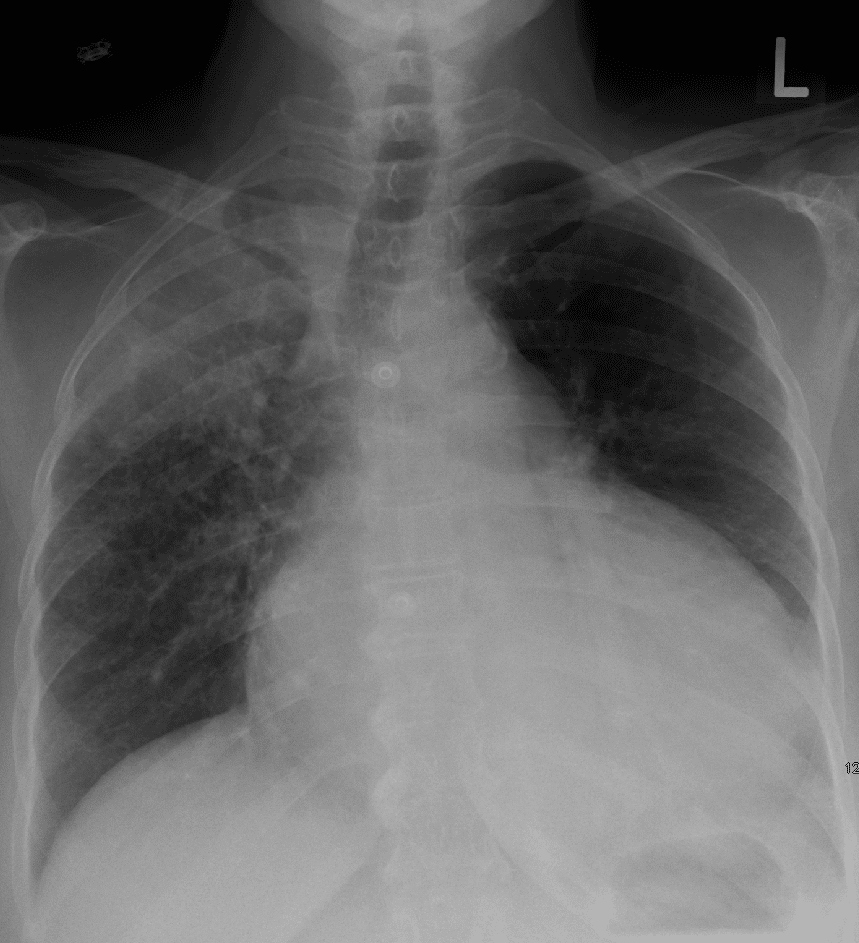

Fig 4

Radiographic appearance of pericardial effusion (note the enlarged heart shape).